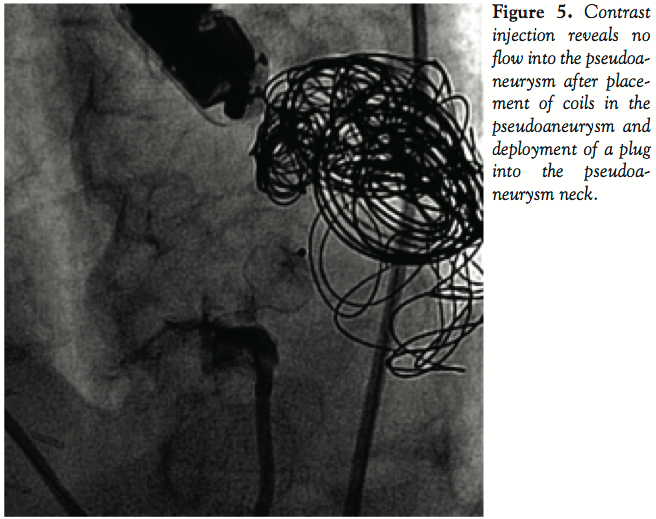

the glidewire was removed. Eighteen embolization coils of different lengths were advanced into the aneurysm cavity. The neck of the pseudoaneurysm was occluded using a 12 mm AGA Amplatzer II vascular plug. There was no communication between the LV cavity and pseudoaneurysm cavity after the plug was deployed (Figure 5).

The patient did well after the procedure. She did not have further chest pain or dyspnea. She reported significantly increased exercise capacity. Cultures from the pseudoaneurysm cavity were negative. Follow-up echocardiogram 1 month later showed no communication between the left ventricle and previously closed pseudoaneurysm (Figures 6 and 7).